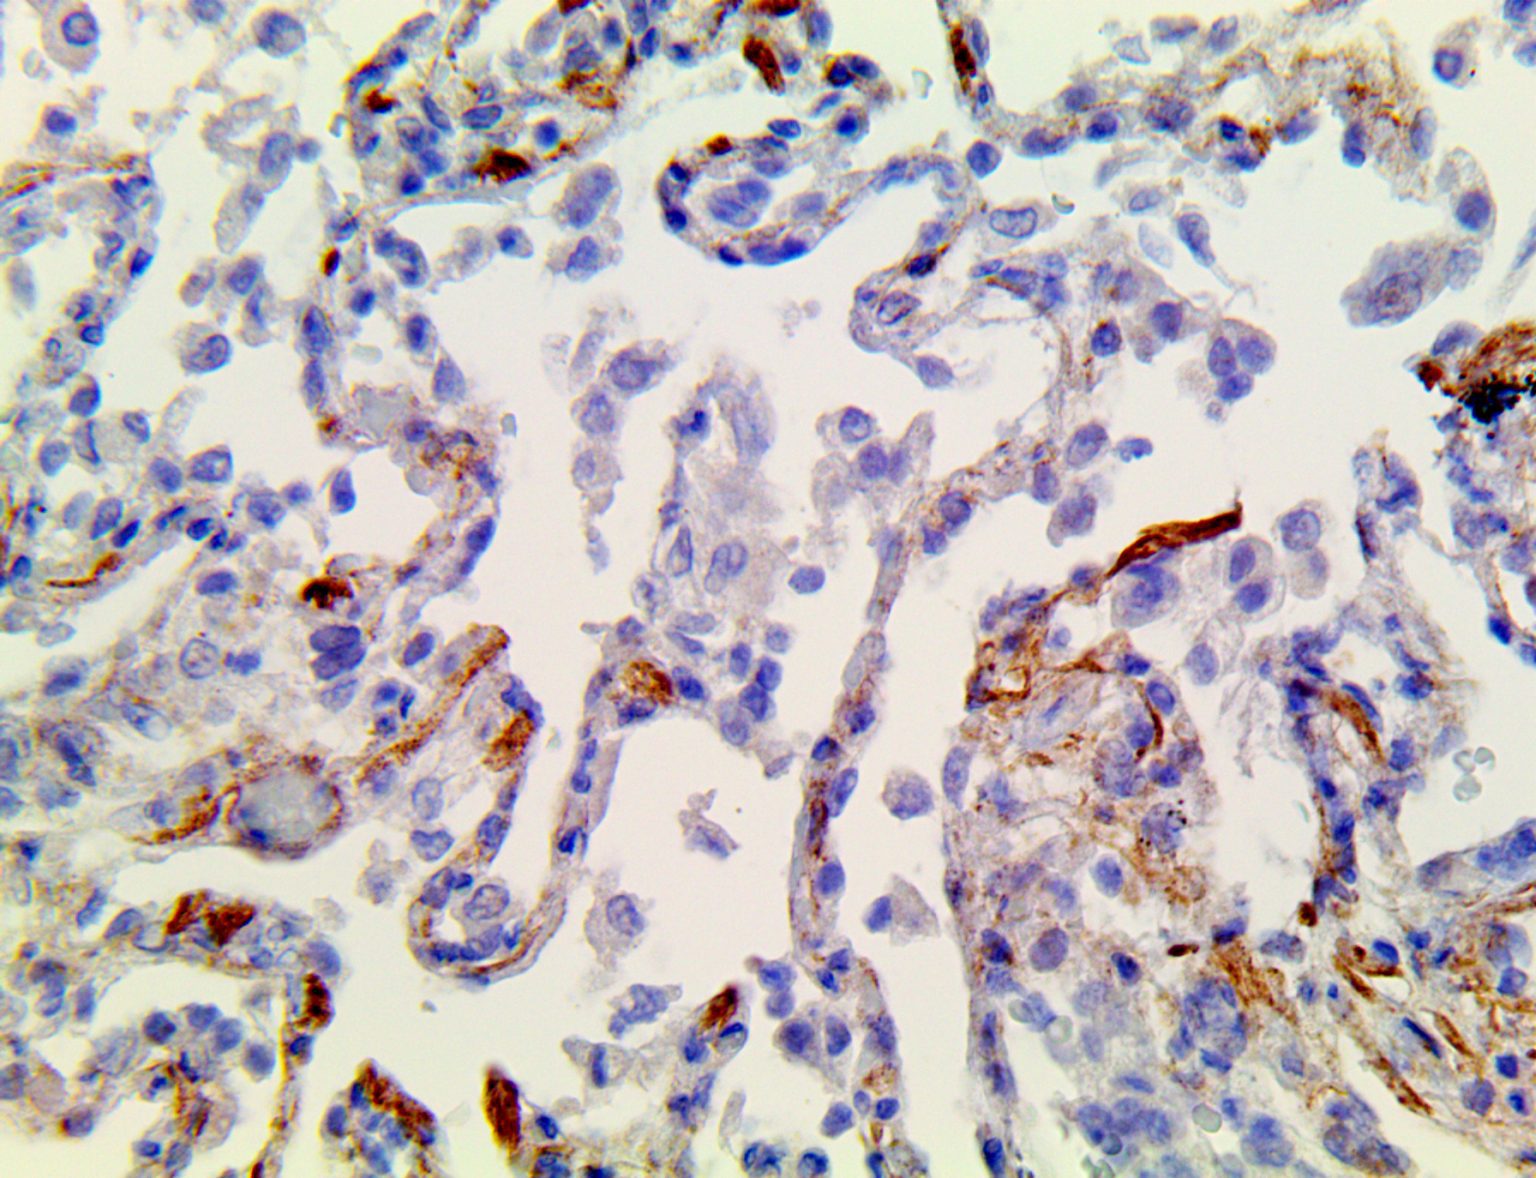

This activation induces inflammatory monocytes to highly express IL-6, starting a localized and then systemic cascade effect that results in hyperproduction of IL-6, which accelerates the inflammatory process. Because IL-6 also increases vascular permeability, excessive levels cause blood vessels to become very leaky. This, along with clotting factors released from vascular endothelial cells, stimulates the coagulation cascade, resulting in microthrombosis (tiny clots), which leads to ischemia and tissue death of the kidney, intestines, heart, liver, brain and extremities.